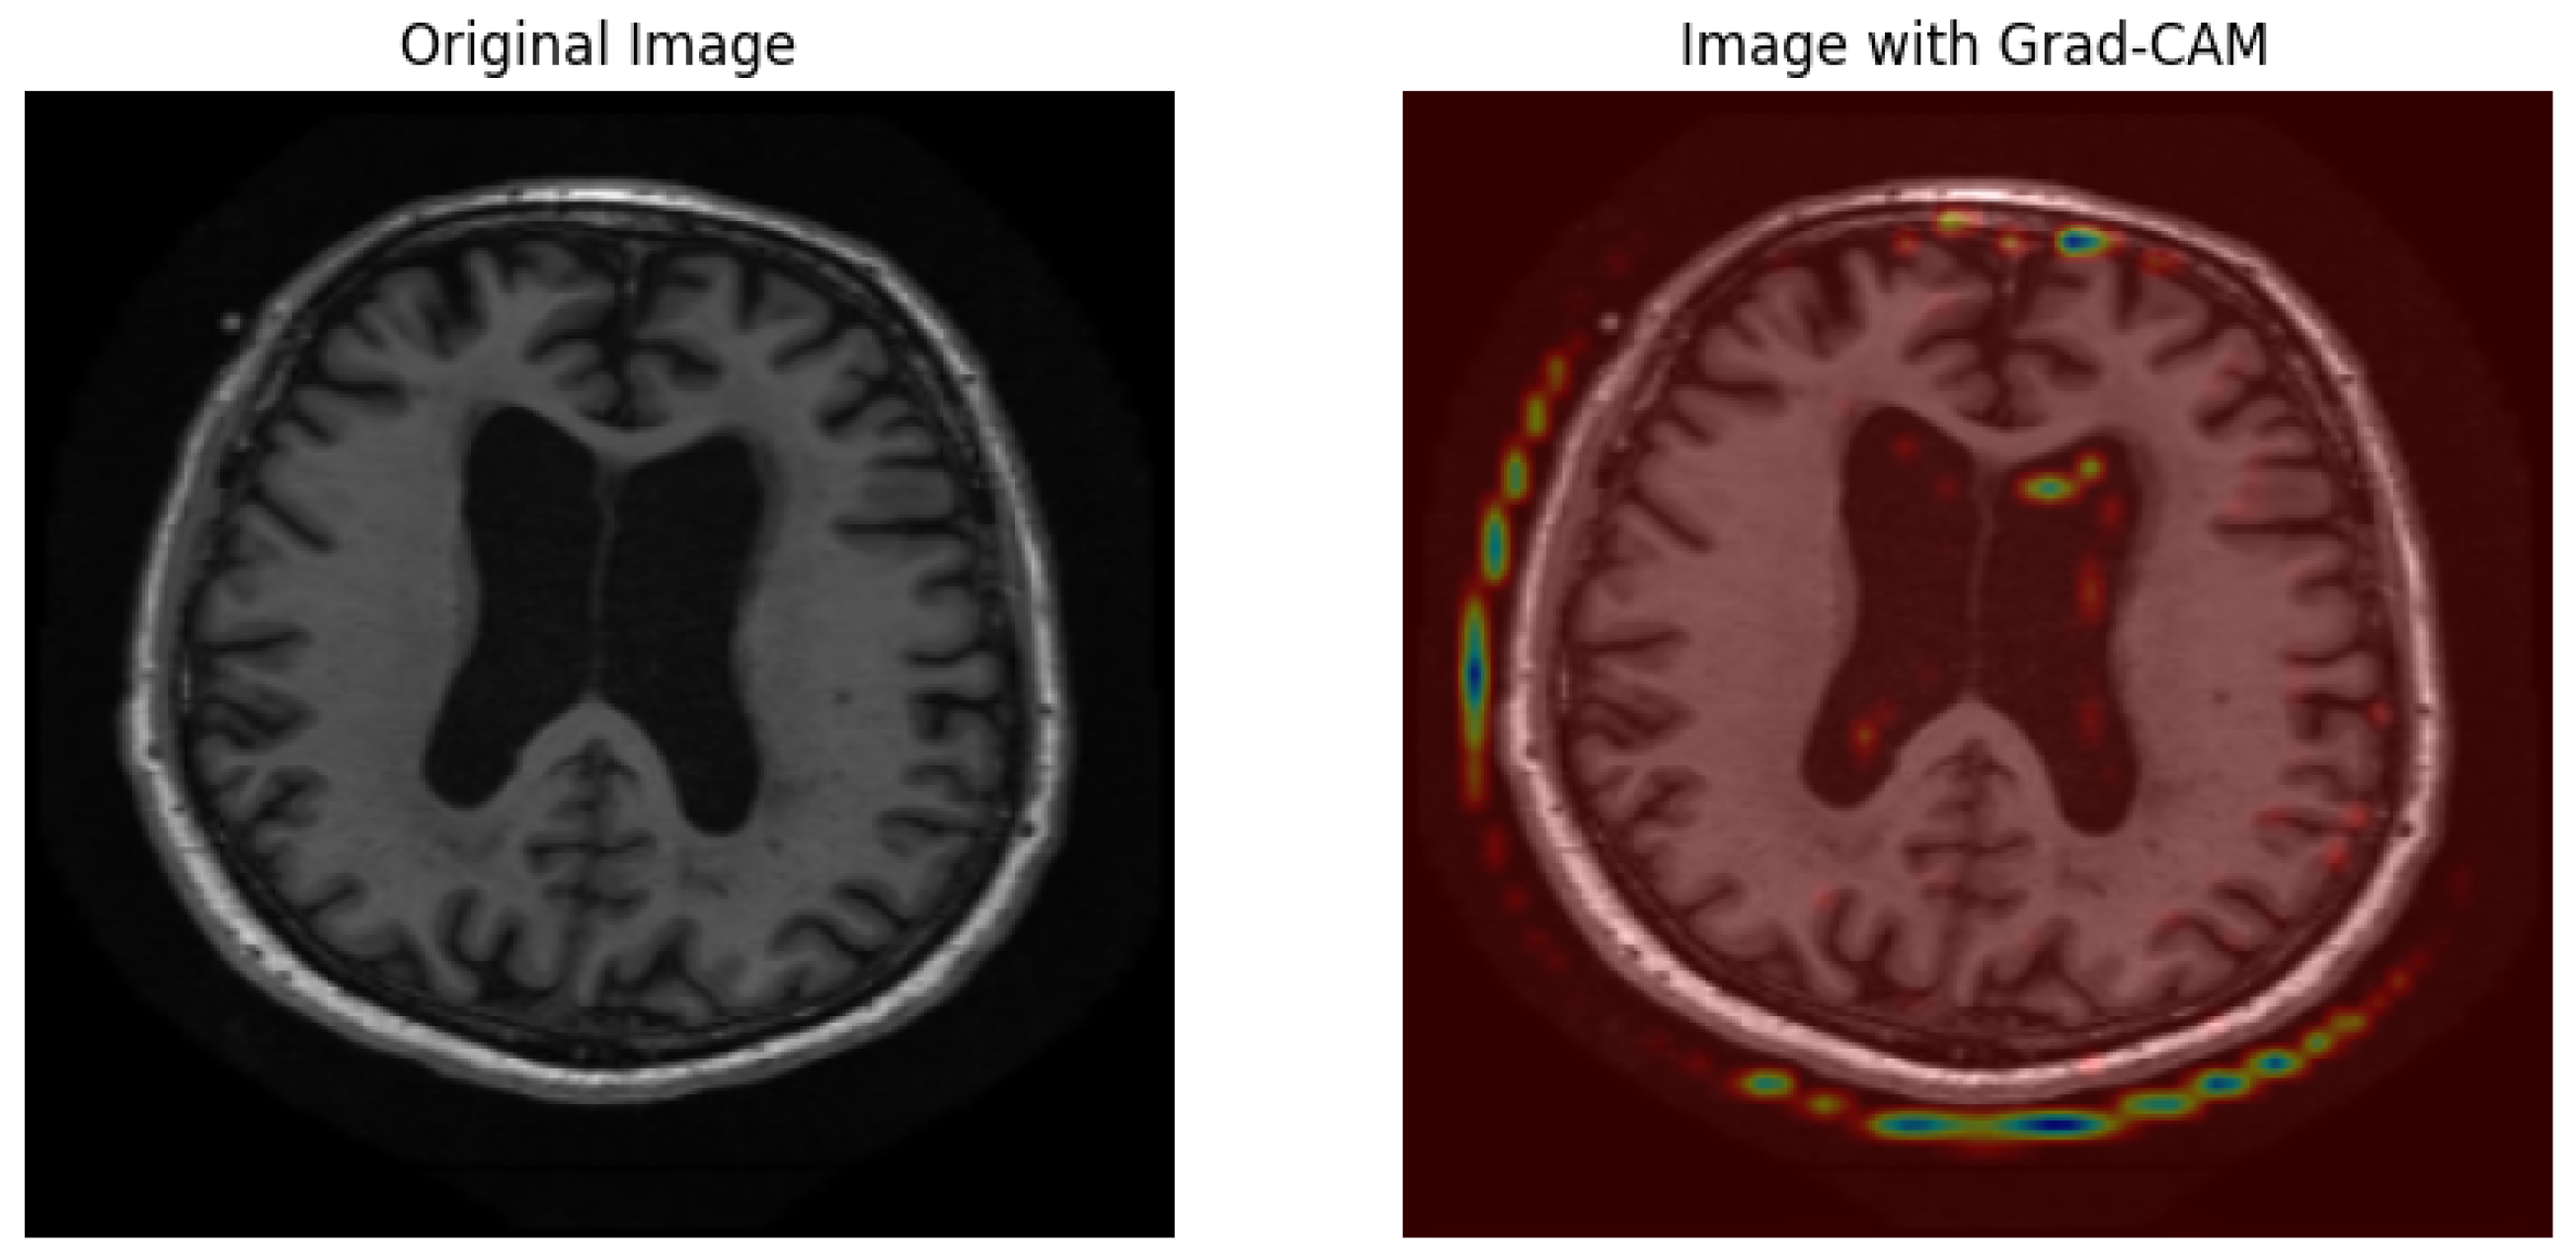

5.1.7. Grad-CAM Results

5.2.7. Grad-CAM